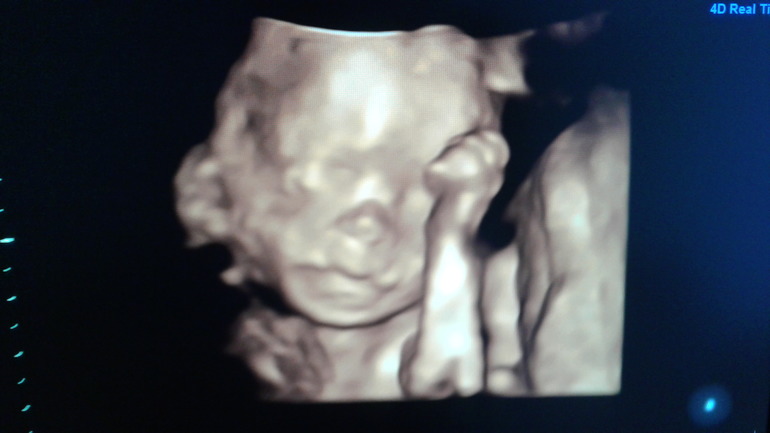

Узи делала в 19,5 недель. Малыш 370 грамм. Соответствует сроку. Дома рассмотрела фотографию, губы папины)))))😄